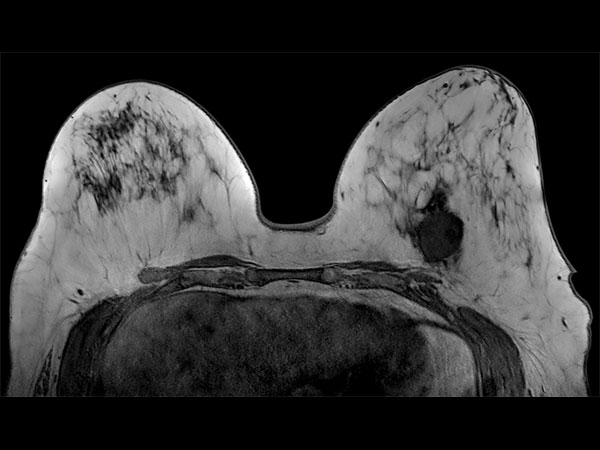

57 year old female with a new diagnosis of Ca. Sample obtained by US biopsy: Invasive Ductal Ca, grade 3. MR requested to aid in determining treatment.

Axial T2w 3D TSE (VISTA)